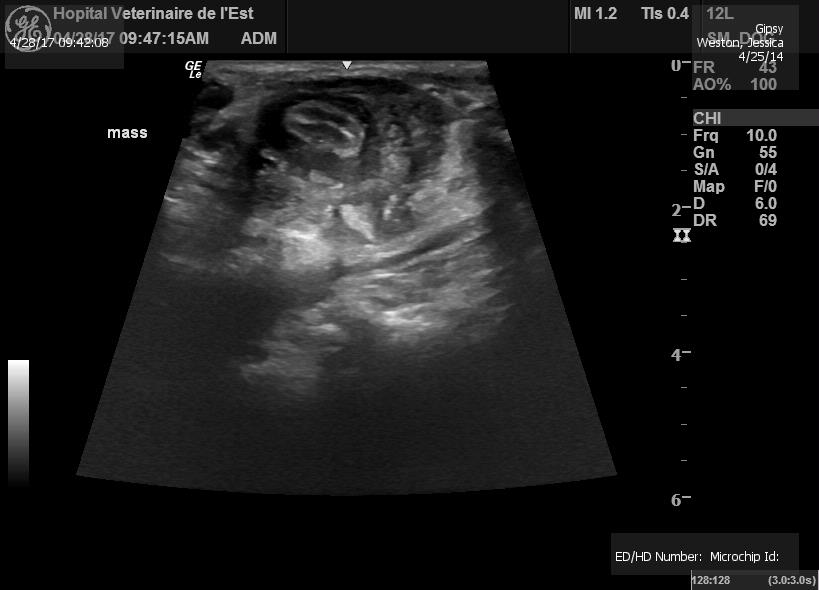

Gypsy has been loosing weight since Christmas. I figured she was depressed, this being her first winter in Canada. When she started loosing her appetite, I decided to bring her in for some test. The vet felt a mass in her stomach so we did some bloodwork and xrays. They weren't conclusive so they sent her for an ultrasound. The ultrasound confirmed she had a 2.5 cm cancerous mass growing in her abdomen. If left untreated, they don't expect her to make it through the summer

Here are pictures of Gypsy fighting Cancer 28/05 :

She has lost all her weight and muscle mass. She is just as skinny as the day we found her. Her energy levels are still high and the vet confirms she is not yet suffering.